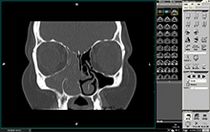

Chronisch-polypöse Sinusitis mit Verlegung sämtlicher Nasennebenhöhlen und der Nasenhaupthöhle (Digitale Volumentomographie, DVT)

Die Diagnostik dieser Erkrankung basiert neben der Beschwerdesymptomatik (Nasenatmungsbehinderung, Schmerzen/Druck, Sekretion, Riechminderung) auf der Endoskopie der Nase und der obligaten Schnittbilddiagnostik der Nasennebenhöhlen. Hierzu verfügen wir über die derzeit modernste Diagnostik – die Digitale Volumentomographie (DVT) –, die eine hochauflösende dreidimensionale Darstellung des Geschichtsschädels, der Nasennebenhöhlen und des Oberkiefers bei im Vergleich zur konventionellen Computertomographie deutlich niedrigerer Strahlenbelastung ermöglicht.